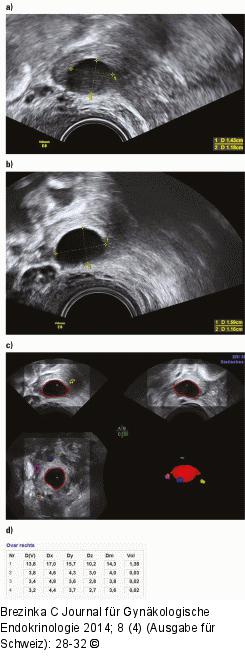

Abbildung 1a-d: Follikelmessung Derselbe Follikel mit verschiedenen Presets: (a) Im Preset „Penetration“ wirkt der Inhalt etwas diffus, (b) im Preset „Ovary“ zeigt sich eine klare Kontur, die (c) wiederum einen markanten Follikel im Sono-AVC ergibt. (d) Der Durchmesser beträgt knapp 14 mm, das Volumen 1,4 ml. |

Derselbe Follikel mit verschiedenen Presets: (a) Im Preset „Penetration“ wirkt der Inhalt etwas diffus, (b) im Preset „Ovary“ zeigt sich eine klare Kontur, die (c) wiederum einen markanten Follikel im Sono-AVC ergibt. (d) Der Durchmesser beträgt knapp 14 mm, das Volumen 1,4 ml. |